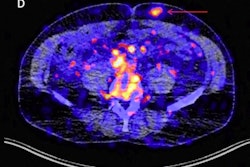

In radiology applications for oral SCC, a convolutional neural network (CNN) was able to predict disease-free survival with 80% accuracy, sensitivity, and specificity from PET images, the researchers reported. Another CNN showed lower performance -- 66.9% sensitivity, 89.7% specificity, and 84% accuracy -- when used on CT for predicting disease-free survival. A deep-learning algorithm also yielded 90% sensitivity for detecting lymph node metastasis from oral SCC on CT.